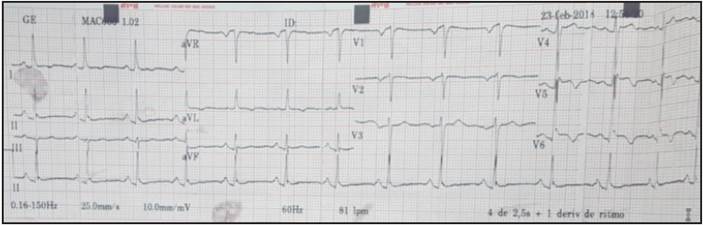

A 58-year-old female patient who only had a history of controlled arterial hypertension and depression (which was currently being treated) presented to the emergency room with a complaint of oppressive retrosternal chest pain beginning one hour before, radiating to the left arm and with an intensity of 10/10 on the analog pain scale; diapho resis; dyspnea; nausea and a feeling of impending doom. The symptoms were triggered by a stressful emotional event. She went to the emergency room where clinical assessment and paraclinical tests documented a possible acute coronary syndrome, such as acute myocardial infarc tion with ST elevation. The admission electrocardiogram showed a sinus rhythm with a normal QRS axis, elevated ST on V5-V6, and an inverted T wave on precordial V4 and V5 with signs suggestive of left ventricular overload; the remaining leads were within normal limits (Figure 1). The chest x-ray showed a slightly increased cardiac silhouette with no evidence of parenchymal infiltrates or pulmonary congestion. The complete blood count and other blood chemistry studies were within normal limits. The cardiac biomarkers showed increased troponin I at 0.283 ng/dL with a 99th percentile reference value of 0.014 ng/ dL. Thus, it was initially considered to be an acute coro nary syndrome of the acute myocardial infarction with ST elevation variety. Since the emergency room was at a quaternary level institution, the patient was transferred in under 120 minutes to the hemodynamics department and a percutaneous coronary intervention was ordered. The study showed: no obstruction of the coronary arteries or their branches, with a left ventriculography suggestive of latero-apical akinesia and ventricular ballooning with a diminished ejection fraction of 40%, suggesting takotsubo (Figure 2). An echocardiogram was performed in the cath lab recovery room which described: a normal-sized left ventricle, without wall hypertrophy, moderately decreased systolic function due to impaired contractility secondary to akinesia of the apex and the apical segments of all the walls, with an estimated ejection fraction of 35% with no evidence of thrombi or intra-chamber masses. The right ventricle had preserved systolic function and a normal valvular plane without pulmonary hypertension.